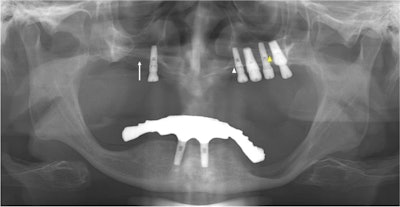

The panoramic x-ray of a 64-year-old man shows that perforation is suspected at the right maxillary sinus floor (white arrow). The white arrow indicates the left hard palate line, while the yellow arrow indicates the antral floor.

An x-ray revealed an implant retained in the maxillary right canine area just lateral to the right nasal cavity. A CBCT scan showed obvious discontinuity of the inferolateral cortex of the nasal cavity and oronasal fistula. This was observed as a tissue defect on panoramic x-ray, according to the report.